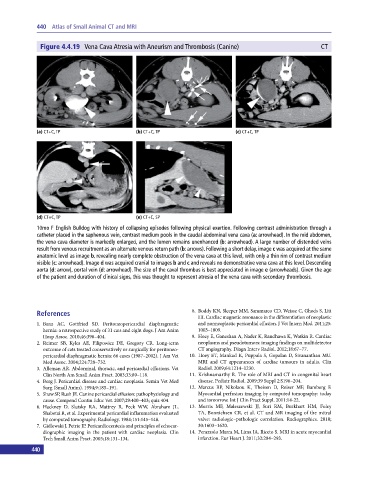

Figure 4.4.19 Vena Cava Atresia with Aneurism and Thrombosis (Canine) CT

(a) CT+C, TP (b) CT+C, TP (c) CT+C, TP

(d) CT+C, TP (e) CT+C, SP

10mo F English Bulldog with history of collapsing episodes following physical exertion. Following contrast administration through a

catheter placed in the saphenous vein, contrast medium pools in the caudal abdominal vena cava (a: arrowhead). In the mid abdomen,

the vena cava diameter is markedly enlarged, and the lumen remains unenhanced (b: arrowhead). A large number of distended veins

result from venous recruitment as an alternate venous return path (b: arrows). Following a short delay, image c was acquired at the same

anatomic level as image b, revealing nearly complete obstruction of the vena cava at this level, with only a thin rim of contrast medium

visible (c: arrowhead). Image d was acquired cranial to images b and c and reveals no demonstrative vena cava at this level. Descending

aorta (d: arrow), portal vein (d: arrowhead). The size of the caval thrombus is best appreciated in image e (arrowheads). Given the age

of the patient and duration of clinical signs, this was thought to represent atresia of the vena cava with secondary thrombosis.